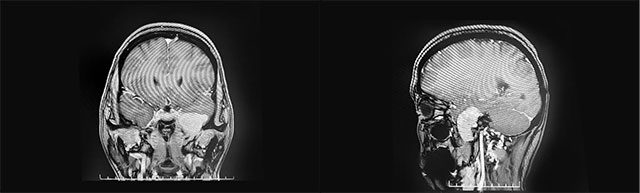

▲ 肿瘤位于左侧颅中窝颞叶内侧底部

头颅MRI平扫+增强显示:左侧颅中窝颞叶内侧底部见一肿块影,矢横高径约3*4*3cm,边缘尚清晰,形态不规则(局部向左侧桥小脑角略凸起),毗邻左侧颞叶、桥脑脑组织受压内移,增强扫描显著明显强化(向左侧桥小脑角凸起灶环状强化)。

结合患者病情和影像学检查,潘仁龙主任、李士其教授、吴治群博士会诊后指出,考虑为神经纤维瘤。正是肿瘤压迫三叉神经导致其面部麻木疼痛,患者手术指征明确,应尽快手术。